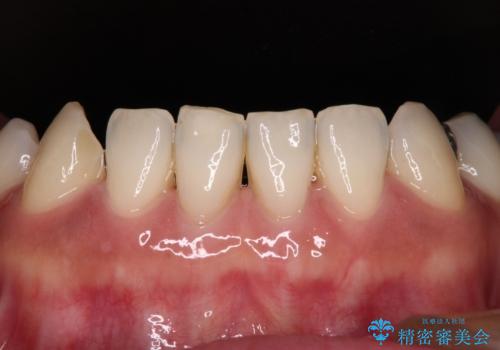

中途半端な矯正治療と前歯の欠損 再矯正とオールセラミッククラウンによる補綴治療

- 矯正治療を行ったものの、隙間やデコボコが多く、欠損している前歯も気になるとのことで来院された患者様です。

当初はセラミック治療だけを希望されていましたが、上下前歯のデコボコが顕著であったため、セラミッククラウンにて治療する前に再度矯正治療を行った方が仕上がりがきれいになると説明し、再矯正を行うこととしました。

矯正治療により前歯横幅のバランスを整えた後に、上顎前歯をオールセラミックブリッジにて補綴治療を行うこととしました。